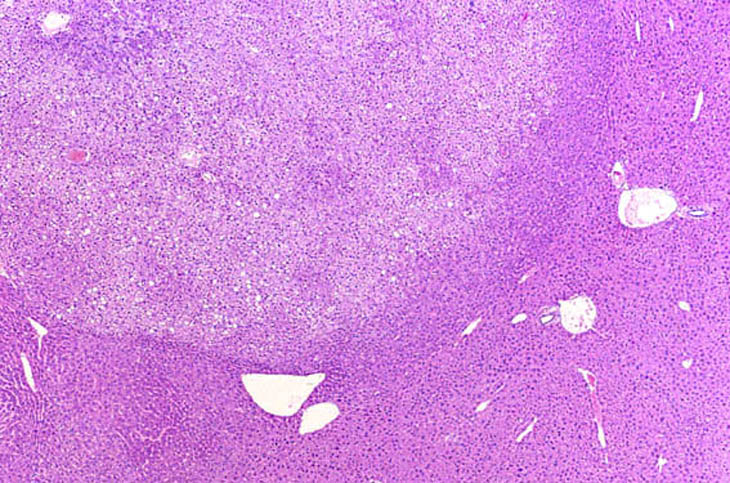

This adenoma has a partial rim of basophilic cells while the remaining cells are pale.

This mixed hepatocellular adenoma is comprised of an admixture of basophilic and pale staining hepatocytes.